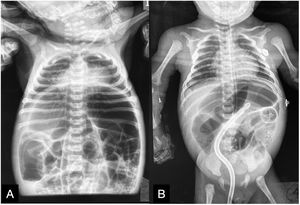

A plain abdominal x-ray was ordered, revealing important intestinal segment dilation (Fig. 1A). An orogastric tube was placed, with abundant output of bile, and a transrectal tube improved the abdominal distension (Fig. 1B). The infant had clinical signs of low cardiac output that responded to dobutamine infusion and presented with oliguria and elevated serum creatinine and blood urea nitrogen. Thyroid panel results were TSH 404 mIU/mL, total T4 0.420ng/dl, T4 0.058ng/dl, total T3 0.195ng/dl, T3 0.321pg/mL, for which treatment with levothyroxine was indicated. Feeding was started with extensively hydrolyzed formula in continuous infusion one week after her admission. Given the clinical presentation consistent with Hirschsprung’s disease, a contrast-enhanced barium enema was ordered that revealed an apparent transition zone in the rectosigmoid colon (Fig. 2), and so rectal irrigations were started. A rectal biopsy was taken, and high-resolution anorectal manometry was performed, documenting the rectoanal inhibitory reflex. Pericardial effusion, anemia, elevated direct bilirubin, and elevated transaminases were detected in the complementary evaluations.